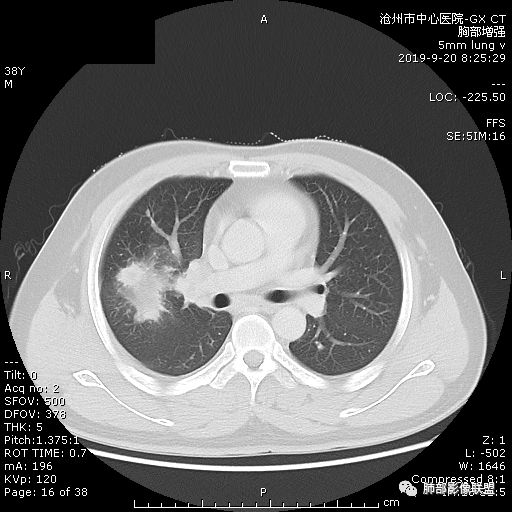

青年男性,肿瘤指标无异,右上中肺团片影,形态不规,跨叶生长,

病灶内见坏死,增强边缘强化,考虑炎性肉芽肿,TB,鉴别鳞。

年轻男性,咳嗽2月,痰中带血,胸痛,炎症指标稍高,肿标正常。影像,右肺上叶不规则团块影,浅分叶,伴边界不清磨玻璃影,从外周向内分布,局部胸膜增厚,病灶中央坏死,坏死边界尚清,空洞形成,空洞内壁光滑;考虑炎性肉芽肿性病变,结核可能,鉴别恶性肿瘤及真菌感染。病灶分布特点不考虑隐球。

右肺上叶不规则病灶,密度不均,有分叶,边缘不清,中央有坏死,坏死壁尚光滑,增强壁有强化,病灶有外朝内,整体收缩为主,慢性病程,考虑炎性病变,肺脓肿或者结核,淋巴结肿大,支气管截断,胸膜脂肪间隙变窄,加个鉴别恶性肿瘤。

近端支气管截断,非坏死区的强化特征,肺门区肿大淋巴结,所谓的“月牙铲”,这些强烈提示病变是癌;胸膜、相邻肋间肌的改变,提示是炎性改变;在癌与炎性肉芽肿之间,哪个占主导地位?是解决问题的关键;坏死区的形态,也支持炎性病变。

右肺上叶分叶状肿块(冠状位尤为明显),内见液化坏死,支气管截断,收缩力强,周围有片状影,右侧腋窝及纵隔淋巴结增大,增强有强化,定性恶性病变,脓肿形态及临床症状不符,暂排除。

右上肺占位,总体膨胀性生长,支气管截断,坏死明显,常规考虑鳞。

38岁,男性,慢性咳嗽2月,右胸痛8天,无发热;白细胞高,肿瘤标志物不高;右上肺不规则块状影,周围有磨玻璃影,边界清,整体有膨胀感,分叶,与胸膜糊墙,并见栽赃,增强肿块中央坏死,周边强化。综合考虑,考虑恶性,鳞癌可能。

38岁,男性,慢性咳嗽2月,右胸痛8天,无发热。白细胞高,肿瘤标志物不高。右上肺不规则块状影,周围有磨玻璃影,边界模糊,整体有膨胀感,分叶,与胸膜糊墙,可疑栽赃,增强肿块中央坏死,边界清,周边强化明显,强化区有低密度影,壁不规则,跨叶生长,支气管截断,伴支气管扩张,综合考虑腺癌

中年男性,咳嗽2月,伴胸痛8天,少许痰血,无发热中性粒明显增高,低氧,肿标不高,右肺上叶不规则实性肿块,深分叶,局部凹陷呈月牙铲改变,多坏死,多空泡,前段支气管分支似见堵塞,2R、4R、10R和7区淋巴结肿大。考虑肺癌可能,建议支气管镜活检

晨读病例,右肺上叶胸壁处占位,边缘分叶毛刺,收缩力强,多发坏死,远端支气管截断,不均匀性强化,血管穿行变窄,纵隔多发淋巴结肿大,考虑恶性肿瘤,首先考虑腺癌

膨隆、深分叶,支气管截断,叶裂推移,淋巴结肿大,均提示恶性可能;但毕竟年轻,血象高,内部坏死边界清晰,局部收缩感,提示感染可能,另外内部数个小空洞改变,是扩张支气管吗?需要连续层面看,如果是,就更支持感染。

右肺上叶不规则实性肿块,有膨胀有收缩,多坏死,空泡,右肺门淋巴结肿大,考虑肺癌,就是才38岁,太年轻了

晨读:青年男性,咳嗽痰中带血,亚急性起病,白细胞高,超敏高,CT示右肺上叶分叶肿块,内部坏死,病灶周围小结节,近端支气管通过,纵隔淋巴结肿大,综合考虑肉芽肿型结核较鳞癌可能大

晨读:右肺上叶不规则团块,深分叶,膨胀为主,有部分收缩,叶间裂牵拉上移,内多液化坏死,有支气管扩张,右肺上叶大支气管近端通畅,远端堵塞,说明肿块来源于外周,纵隔及右肺门淋巴结肿大,胸膜糊墙为主,年轻人,肿标不高,炎性指标高,综合考虑炎性肉芽肿放前面脓肿,结核,肿瘤放后面。

良孑: 晨读病例,右上肺不规则实变,边界模糊,内可见多发坏死灶,腔内坏死壁厚薄不均,有支气管截断,强化时病灶内血管受累,右肺门淋巴结肿大,从影像上看恶性鳞癌征象较多,但病变明显强化,且坏死壁是均匀强化,炎性标志物高,患者年龄较轻,病史较长,病灶内多个坏死液化灶且内缘光整,综和判断,首先考虑亚急性肺脓肿,其次考虑鳞癌

病灶垮叶,强化明显,病灶内见坏死、空泡,周围模糊,考虑放线菌病?鉴别鳞癌

青年男性,右肺上叶肿块,分叶,明显膨隆,内见空洞与支气管相通,增强环形强化,中心液化坏死。实验室鳞癌指标不高。考虑:1,结核,2,肺脓肿。鉴别鳞癌。

中年男性,咳嗽2月病史伴胸疼。白细胞及中性粒细胞高。右上肺团块影,边缘平直内收,与胸膜宽基底相连,胸膜肥厚,肿块内多灶性坏死,有空泡征,支气管进入,走行自然,近端有阻塞,考虑感染性疾病,肺脓肿。但是有深分叶,鳞癌合并感染也不排除。

右肺上叶不规则病灶,密度不均,有分叶,边缘不清,中央有坏死,坏死壁尚光滑,增强壁有强化,考虑肺脓肿或者结核,但是淋巴结肿大,支气管截断,不除外肿瘤。

首先病灶示:跨尖、后、前三段,局部突入中叶;大家理解一下:是不是光滑的地方有叶裂,毛糙的地方没叶裂。

这个病变两侧受叶裂的局限,中央没有,如果是穿透叶裂的是否边缘也毛糙?事实上这叶裂边缘的叶裂是很光滑的,我倾向于这个是局部叶裂有缺陷;就是从缺陷处进来有病灶的本色:边缘毛糙;附近叶裂的阻挡,边缘光滑;既然怀疑是局部的缺陷就对良恶性没价值。